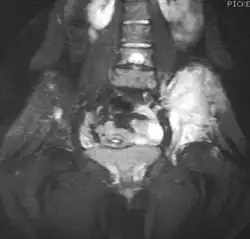

Magnetic resonance imaging slice showing Ewing sarcoma of the left hip (white area shown right)

Magnetic resonance imaging (MRI) should be routinely used in the work-up of malignant tumors. It will show the full bony and soft tissue extent and relate the tumor to other nearby anatomic structures (e.g. vessels). Gadolinium contrast is not necessary as it does not give additional information over noncontrast studies, though some current researchers argue that dynamic, contrast-enhanced MRI may help determine the amount of necrosis within the tumor, thus help in determining response to treatment prior to surgery.[27]

Computed axial tomography (CT) can also be used to define the extraosseous extent of the tumor, especially in the skull, spine, ribs, and pelvis. Both CT and MRI can be used to follow response to radiation and/or chemotherapy. Bone scintigraphy can also be used to follow tumor response to therapy.[27]